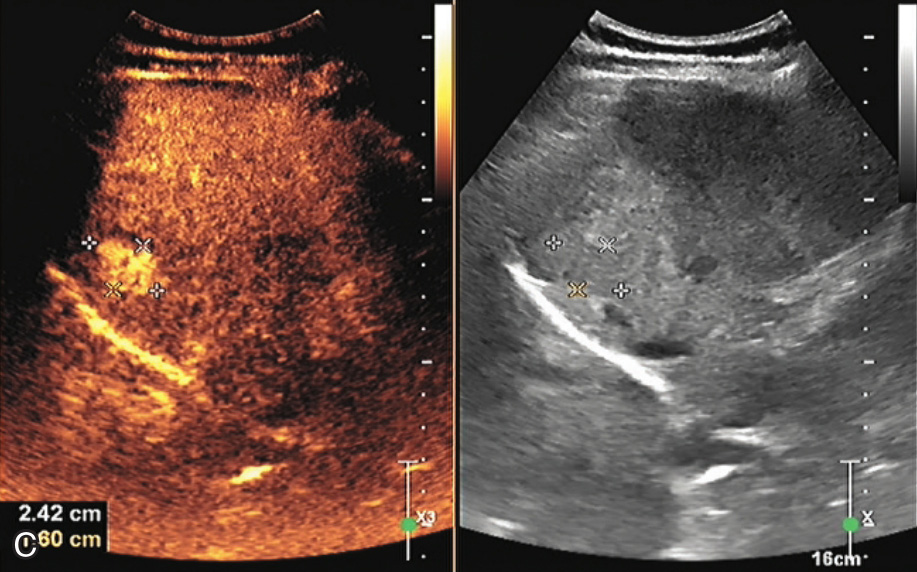

(3)彩色血流特征:

肝腺瘤的血供较丰富,病灶内部及周边可见线状或分枝状血流信号(图1-5-1B)。较大病灶周边可探及粗大迂曲的动脉血流进入病灶内,且阻力指数(resistance index,RI)<0.60。